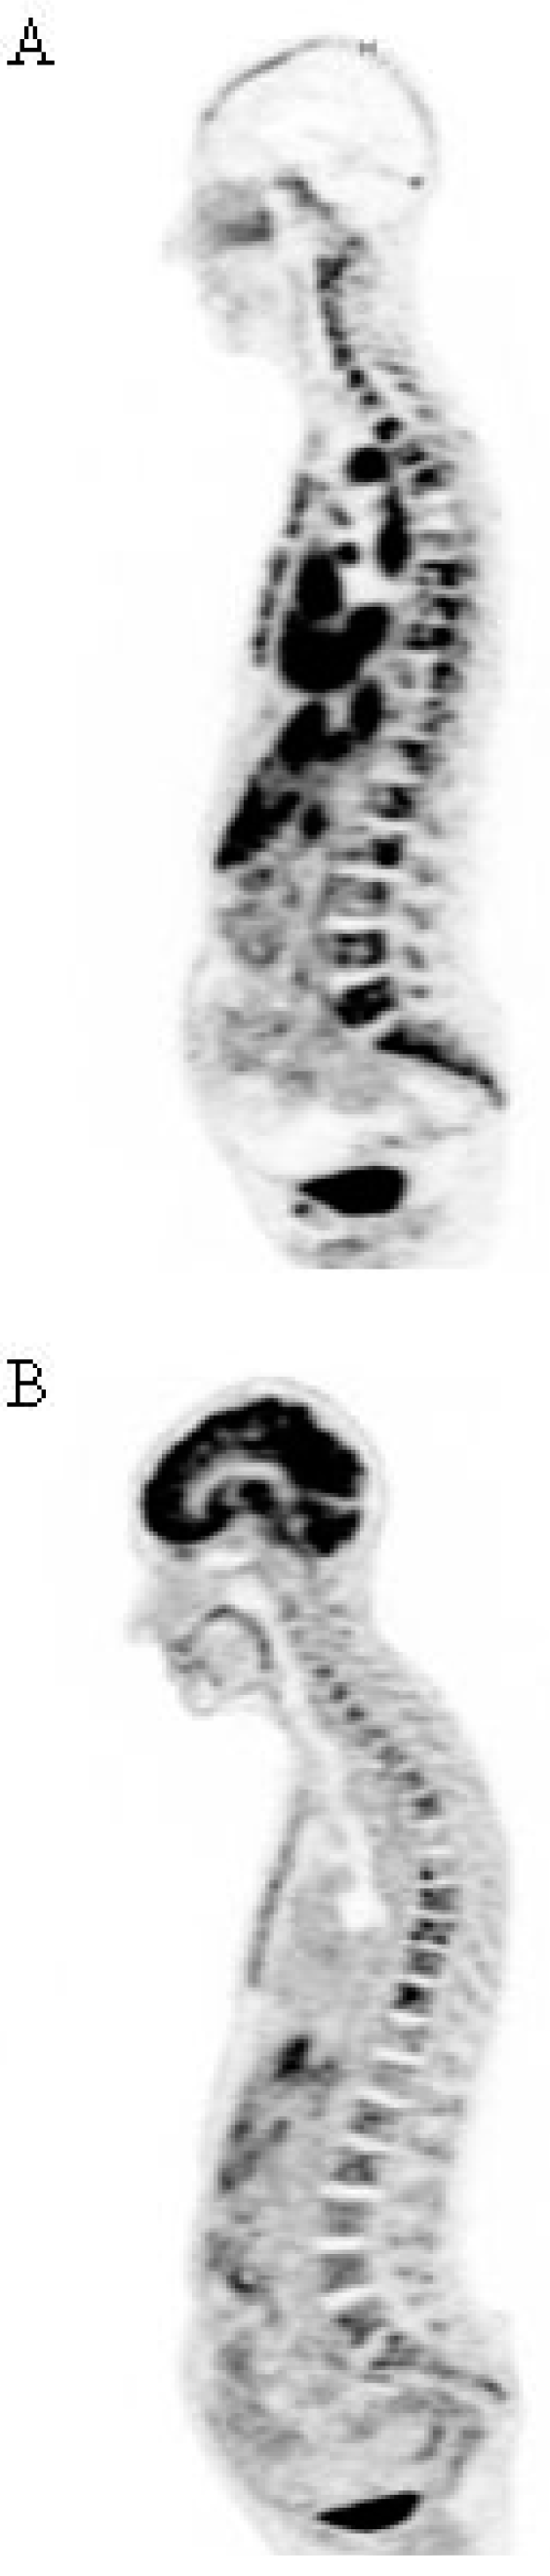

- Tagawa, S.T.; Milowsky, M.I.; Morris, M.; Vallabhajosula, S.; Christos, P.; Akhtar, N.H.; Osborne, J.; Goldsmith, S.J.; Larson, S.; Taskar, N.P.; et al. Phase II Study of Lutetium-177-Labeled Anti-Prostate-Specific Membrane Antigen Monoclonal Antibody J591 for Metastatic Castration-Resistant Prostate Cancer. Clin. Cancer Res. 2013, 19, 5182–5191. [Google Scholar]